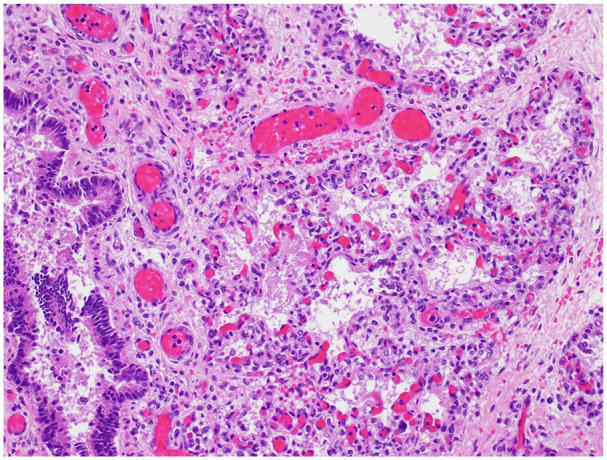

Acute respiratory distress in a neonate is a potentially critical condition with multiple possible causes. Developmental etiologies are particularly problematic by virtue of being refractory to routine modalities for enhancing ventilation and oxygen exchange. Some genetic causes of neonatal respiratory distress, such as surfactant protein deficiencies and alveolar capillary dysplasia with misalignment of pulmonary veins, are well known, and sequencing panels have been formulated to detect them. We present a case of fatal neonatal respiratory insufficiency in which the autopsy showed primary pulmonary hypoplasia and congenital alveolar dysplasia. A sequencing panel of genes associated with heritable pulmonary disorders gave a normal result; however, a chromosomal microarray identified a heterozygous deletion encompassing the TBX4 gene on chromosome 17. Haploinsufficiency for TBX4 is a known cause of disturbed pulmonary development. This case illustrates why work-up of pulmonary developmental disorders must look beyond standard sequencing panels in some instances, if rare causes of pulmonary maldevelopment such as deletions causing haploinsufficiency are not to be missed.